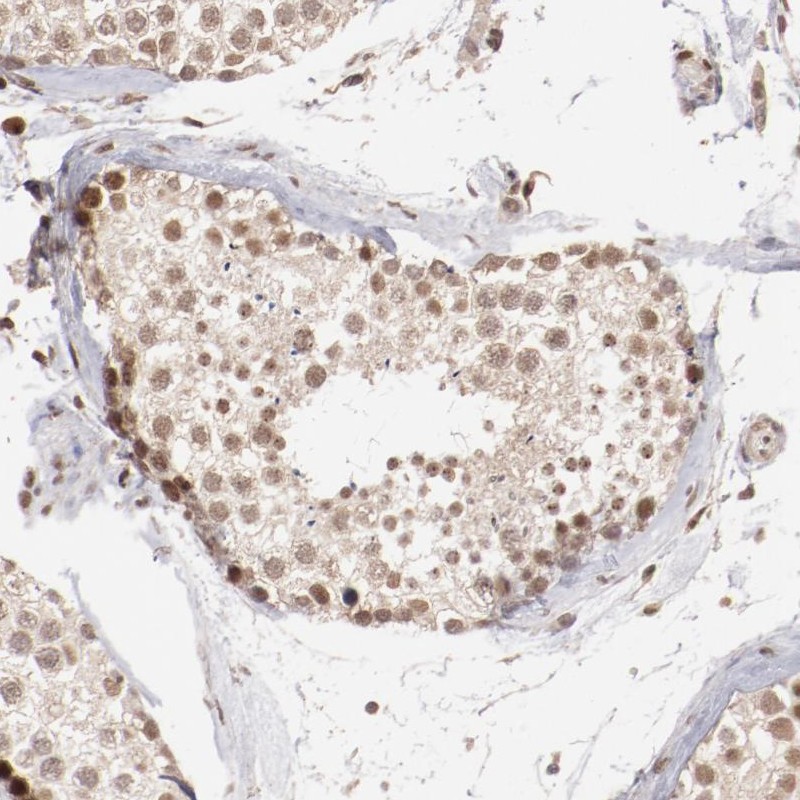

Immunohistochemical staining of human testis shows moderate nuclear positivity in cells in seminiferous ducts.